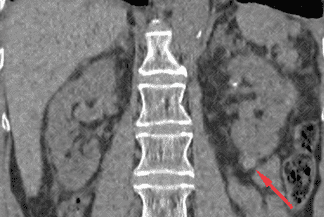

Texto alternativo para a imagem Figura 1. Créditos: Dra. Elazir Mota - Rio de Janeiro/RJ

Descrição da figura 1: Presença de imagem hipodensa no terço médio do rim direito, sem septações ou conteúdo sólido no seu interior, compatível com cisto simples - Bosniak I (seta vermelha).